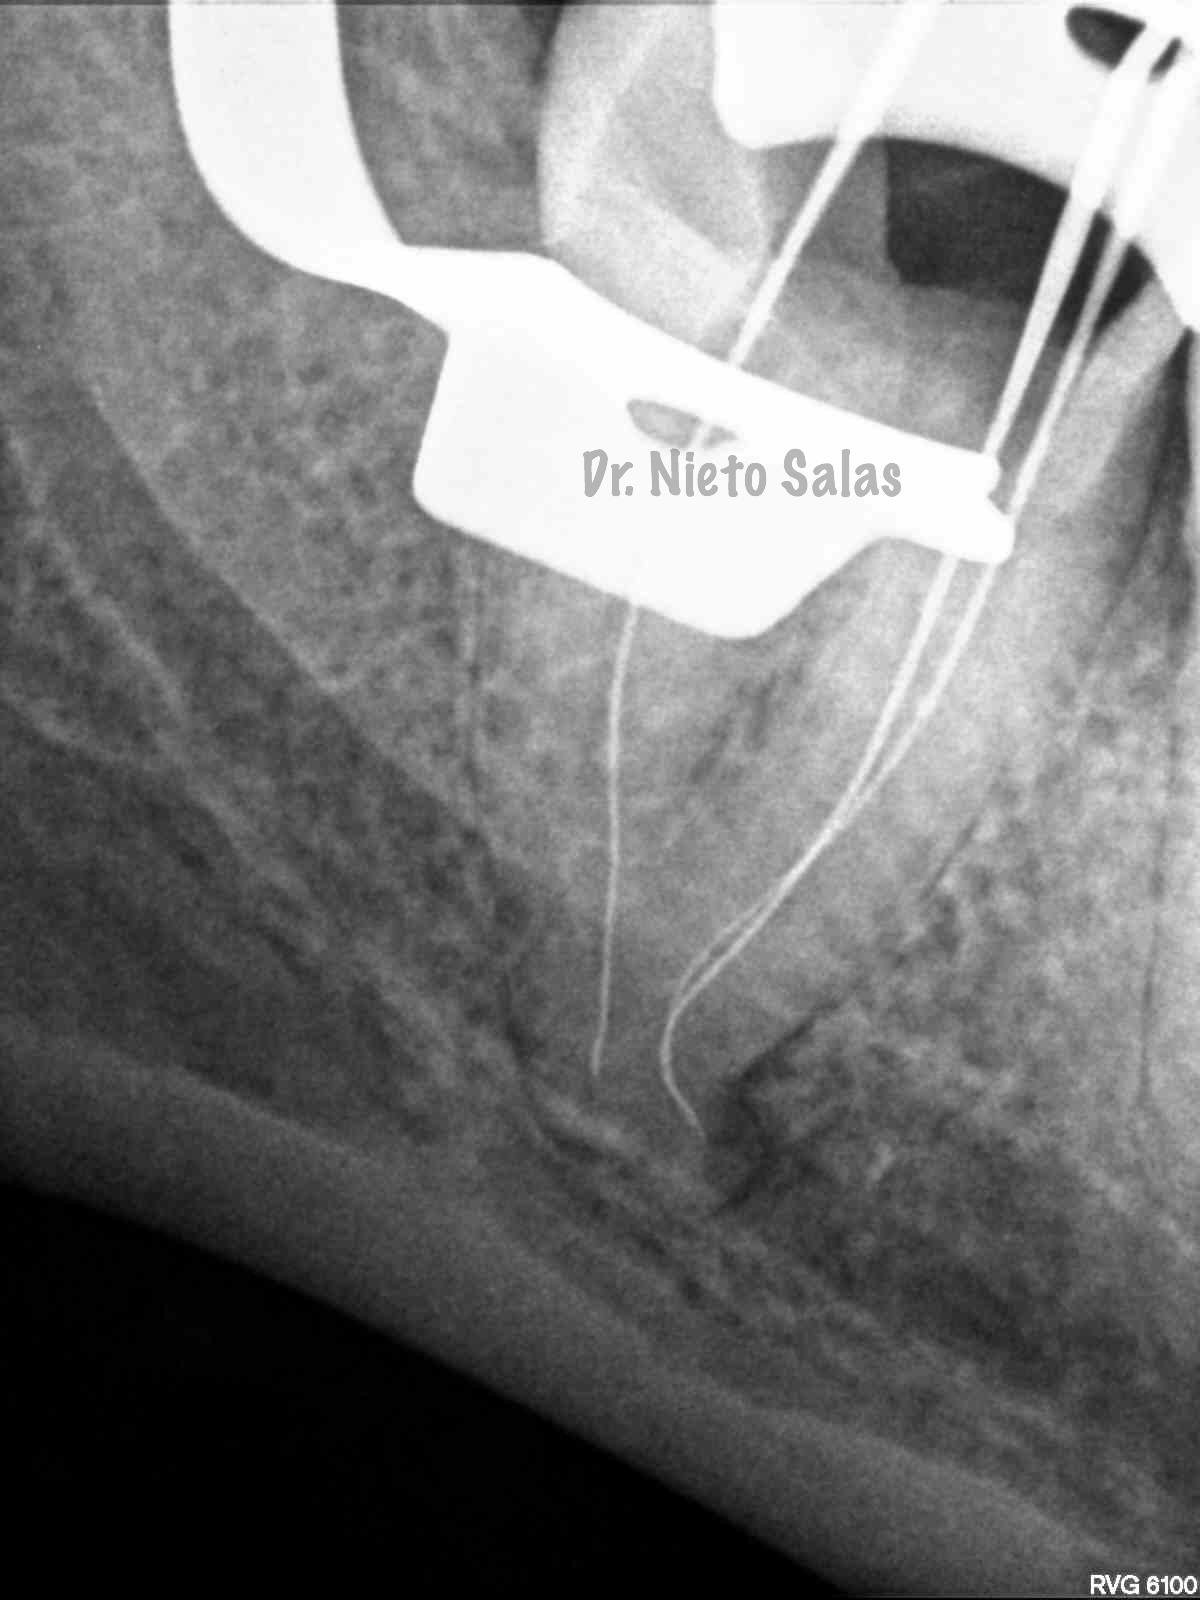

Bueno , ante esta piezas, que presentan una periodontitis apical crónica en la 4.7 y una pulpitis irreversible en la 3.7 nos disponemos a realizar le tratamiento de conductos.

Intentamos mantener la permeabilidad y la forma de  los conductos. Instrumentamos con Pathfile y Mtwo hasta un 25-6%.

(ORTO)                                                               (DISTO)

(MESIO)